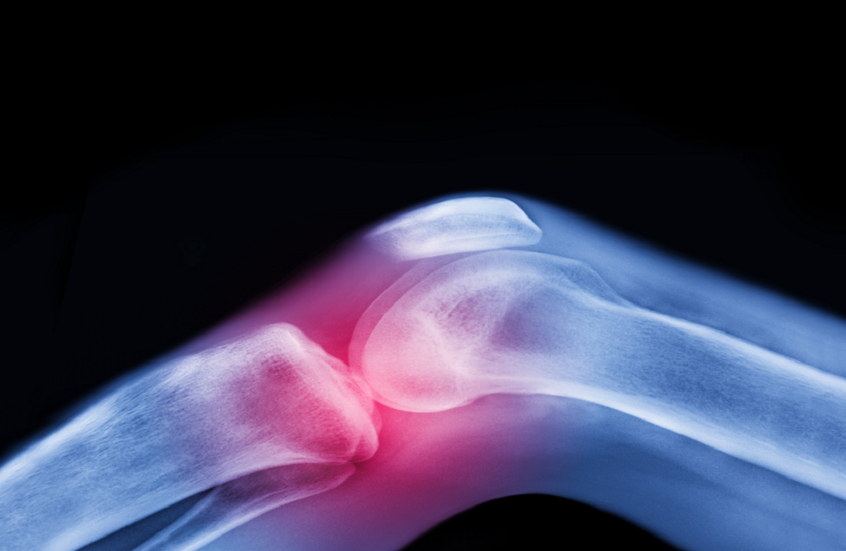

تعتبر آلام المفاصل وتيبّس الركبتين وأوجاع الوركين من الشكاوى الشائعة بين كبار السن، وغالبا ما يُقبل بها كجزء طبيعي من أعراض الشيخوخة.

صورة تعبيرية / Peter Dazeley / Gettyimages.ru